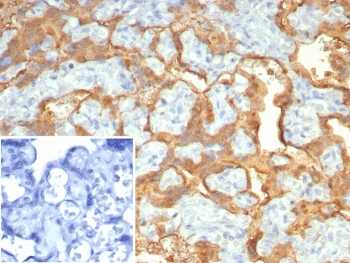

Cathepsin D Antibody

| Description | Cathepsin D Antibody |

| Tested applications | FC, ICC, IHC, IP, WB |

| Reactivity | Human, Mouse |